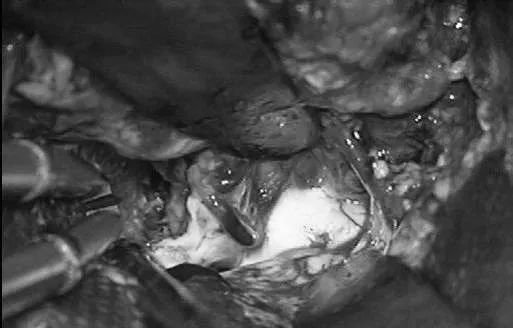

颞角AVM切除像颞底AVM一样通过颞部开颅(1步)、通过颞下回(ITG)经皮质入路。病人取仰卧位,头向侧方偏转90°,降低顶点以获得一朝向颞角的向上的角度。以耳上为基底的马蹄形切口、颞部开颅。入路在颞下回下部,角度对着脑室,保持在Meyer’s环内的视放射之下。Meyer’s环从上面越过颞角(2步)。导航有助于确定该入路。一旦进入颞角,沿其轴纵向打开,以完整看到AVM。直到切除结束才能够看到下ChorV和BVR(3步)。在脉络裂近端丛点之后辨认AChA,在脉络裂远端病变之后可见lPChA供血(4步)。先阻断AChA供血血管(5步),但是另外的自脉络丛的供血血管在内侧缘,从近端向远端继续分开脉络裂阻断这些脉络丛供血血管。需要向前用力,将一部分AVM移向外侧(6步)。优先通过脉络丛和穹窿伞(伞带)之间的脉络膜,从下方打开脉络裂,避开上面的尾状核尾部和丘脑下部。然后一步切除的是汇入BVR的引流静脉和残留的来自lPChA的供血血管(7步)。虽然没有严格意义上的语言功能,但是像其它脑室AVM一样,颞角AVM与丘脑、尾状核(尾部)、穹窿(伞)和海马相邻。

(d)6步,沿脉络裂由近及远分离(冠状断面观)。

(e)7步,将AVM移出脉络裂,以切断lPChA供血,辨认环池内的BVR。